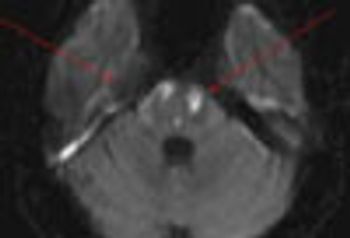

Brain infarcts among crack cocaine users may be secondary to large cerebral artery vasospasm with secondary intravascular thrombosis (with or without distal embolization).